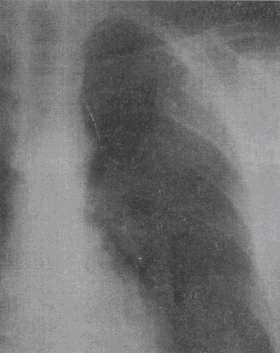

1.男性,50歲。涕中帶血絲1個月余,無發熱及咽部腫痛。CT檢查見圖所示,應首先懷疑以下何種疾病

A.鼻咽癌

B.咽旁膿腫

C.咽部淋巴結炎

D.喉癌

E.神經纖維瘤

正確答案:A解題思路:鼻咽癌病理上主要包括鱗狀細胞癌、腺癌、泡狀細胞癌和未分化癌。按其發展方向可分為上行型、下行型和混合型。